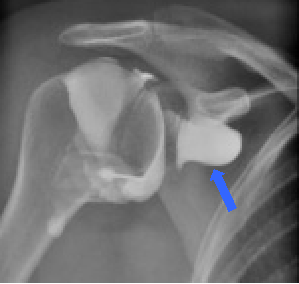

X-ray image of hydrodistension. The x-ray dye is providing a sillhouette of the joint space and dye can be seen escaping where the capsule has ruptured - blue arrow.